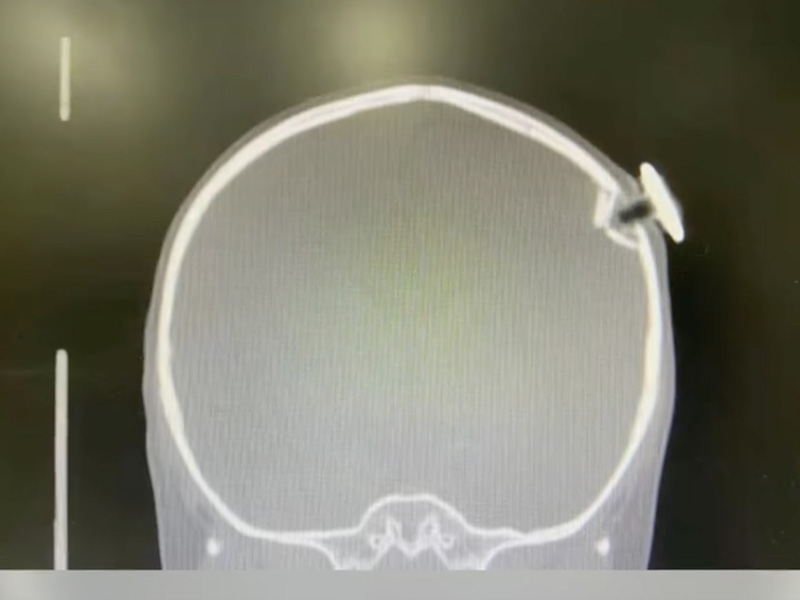

1/6 日,上海一 3 歲女童從床上跌落,正巧砸中一枚朝上的磁力釘。這顆星星型狀的磁力釘撞碎孩子顱骨,扎進大腦約 1.3 厘米,造成左側頂骨凹陷性骨折和腦外出血 ...

這顆星星型狀的磁力釘差點就損傷腦部功能區。

孩子經緊急手術後取出異物,目前已順利脫險。提醒:家長看好孩子!